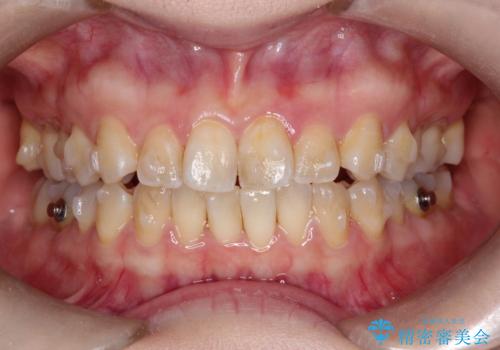

【インビザライン 】前歯の凸凹をなおしたい

- 前歯の凸凹を主訴に来院されました。

インビザライン にて治療を行い、歯並びが綺麗になったと満足していただきました。

前歯のガタガタの量が多かったため、IPR(歯のサイズを小さくするための処置)を行なって治療しました。